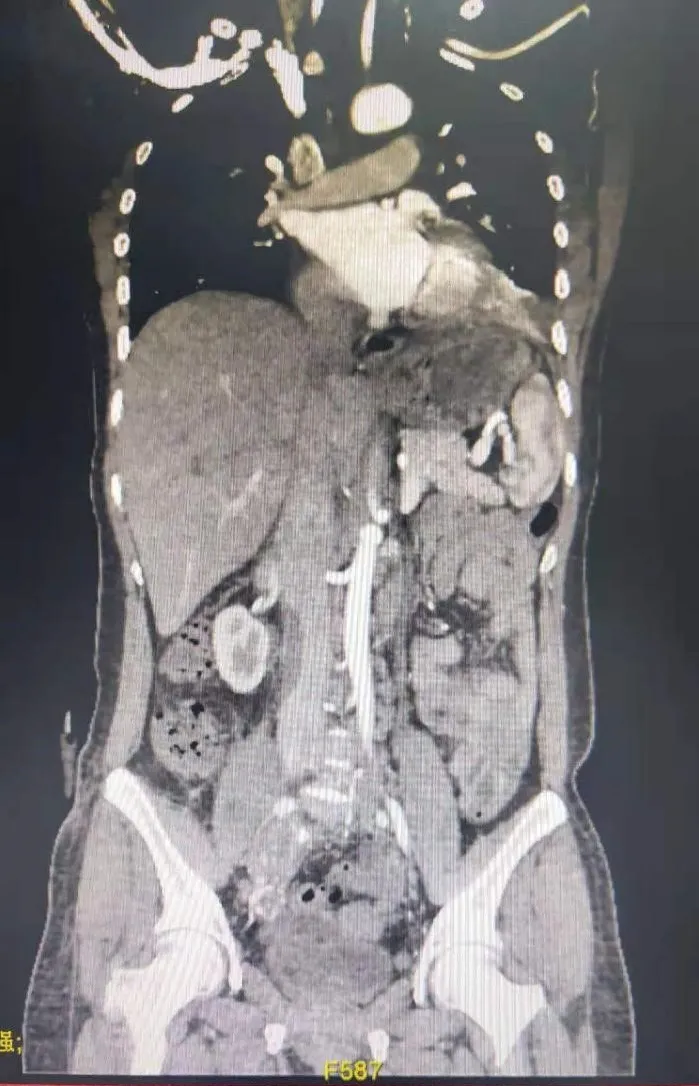

“这个肿瘤非常特殊,它从下往上逆行生长,一直长到了病人心脏里面。”凭着外科医生的敏感直觉,有着二十多年丰富临床经验的孙玉桂副教授第一时间发现了这个“不速之客”的特殊之处:狡猾的肿瘤不但躲在大血管里面,还变成了两个分支进行躲藏,一支藏到了肝脏附近,另外一支则藏进了心脏里面,类似一个“Y”型的形态。由于肿瘤从病人大腿根部一直长到了心房位置,最粗的地方有鸡蛋大小,肿瘤不但体积大、长度长,而且离人体许多重要内脏器官的位置都很靠近,手术当中稍有不慎,后果不堪设想。

怎么才能既保证完整切除肿瘤,又不过度骚扰损伤周围器官?孙玉桂副教授立刻与张立飞教授,展宇飞、肖智宏医师等进行了严谨的讨论:肿瘤从盆腔的右侧髂内静脉作为起始部,到达髂总静脉后就发出两个分支,一支沿着下腔静脉逆行到了肝脏门静脉附近,另一支则沿着下腔静脉逆行向上直接长到了右心房里面,因为下腔静脉是人体下半身所有器官的血液回流必经之路,肿瘤沿着下腔静脉管内生长,血供又比较丰富,如果要行手术切除,将是一个极大的挑战——既要从髂内静脉找出肿瘤的“头部”,还要打开心脏找到肿瘤的一个“尾巴”,并找到肝脏门静脉的另一个“尾巴”,这个过程中要保证肿瘤完整切除,不能撕裂扯断,不能破坏下腔静脉正常形态,不能影响各个器官的正常血液回流,这需要体外循环下保证患者正常体循环供血的前提。不仅需要心脏外科、血管外科、胸外科的专业手术技术,还需要多个外科手术科室的紧密配合、协同支持。

孙玉桂立即与麻醉科、手术室、泌尿外科、胃肠外科、肝胆外科、妇科等多个科室开展了MDT(多学科综合治疗协助组)院内会诊讨论,进行了充分手术前准备、精确设计手术方式、合理评估手术风险。胸心血管外科联合各相关科室,经历了近10个小时的紧张手术后,终于完整地切除了长近45cm的巨大巨长肿瘤。既避免了损伤周围脏器,又没有影响下腔静脉的正常血液回流,也没有影响心脏的正常搏动,这个“浩大工程”终于顺利落下帷幕。

术前术后下腔静脉对比: